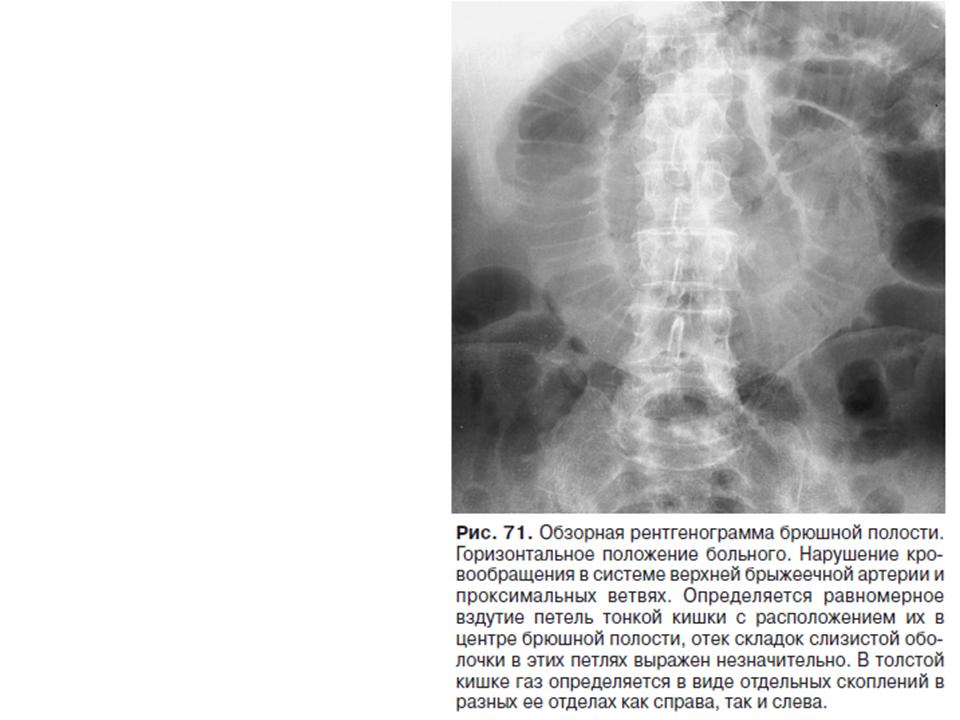

Нормы обзорной рентгенографии брюшной полости